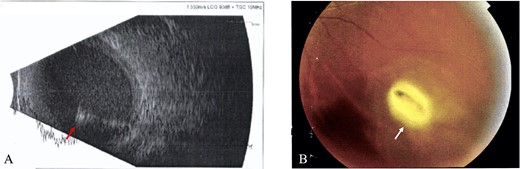

All IOFBs were successfully identified using slit-lamp biomicroscopy, fundus examination, B-scan ultrasonography, plain orbital X-ray, and viewed intraoperatively. Most foreign bodies were intravitreal (four patients, Fig. 1), followed by intraretinal (two patients, Fig. 2), intralenticular (two patients, Fig. 3) and intracorneal (one patient, Fig. 4).

Intraretinal foreign body; (A) B-scan ultrasound revealed hazy vitreous with absence of retinal detachment and high reflective intravitreal object (red arrow), suggestive of metallic IOFB and endophthalmitis (Case 3), (B) Fundus examination showed a foreign body at inferior temporal quadrant of the LE (white arrow), with intraretinal hemorrhage (Case 4).